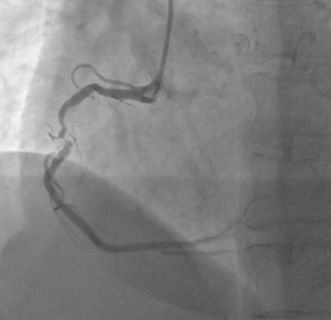

Right Coronary Angiography via right radial artery using 5 Fr TIG Optitorque demonstrated a tight lesion at mid part of Right Coronary Angiography (RCA) with heavy calcification. Left coronary angiography demonstrated non-significant stenosis at Left Anterior Descendent (LAD) and Left Circumflex (LCx) arteries. Therefore, the patient was planned to undergo PCI procedure via femoral access with IVUS guidance and preparation for rotablation.

Diagnostic RCA-1.avi

Diagnostic RCA-2.avi